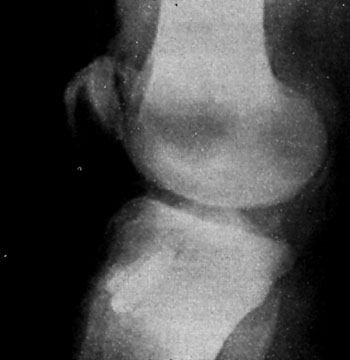

Como metodos complementarios se realizaron radiografias (frente y perfiles), axiales con tecnica de Merchant (pars evaluar el desplazamiento), tecnica de Laurin (21, para evaluar la inclinacion). Encontrando diferentes grados de desplazamiento e inclinacion lateral de la patela de presion del condilo externo. Segun las forma de rotula de Wiberg (1941) se encontraron del Grupo I: 12 pacientes (27%); del Grupo II: 28 pacientes (62%); y Grupo III: 5 pacientes (11%); prevaleciendo por lo tanto la rotula con faceta extema dominante. El angulo "Q" se encontro aumentado en un promedio de 15° (rango de 10° a 18°). En forma sistematica se les realize RMN con contraccion y relajacion de cuadriceps en 20° de flexion de rodilla. Fueron incluidos en el presente estudio el grupo de pacientes que presentaban las caracteristicas de un sindrome de hiperpresion puro o un desplazamiento lateral de la patela menor de 18mm, en la en la evaluacion bajo contraccion cuadricipital en la RMN.

Evaluacion Radiologica y Funcional Post-operatoria Las radiograffas post-operatorias incluyeron frente y perfiles en 30 y 45° de flexion axiales con tecnicas de Merchant y Laurin, que se realizO en el post-operatorio inmediato y a los 2, 3, 6, 9 y 12 meses. La comparacion radiologica se realizo entre los estudios pre y post- operatorios evaluando la inclinacion y el desplazamiento de la rotula. Los cambios radiograficos son irregulares y no indican en algunos casos el resultado clinico obtenido, atin asi, se logra demostrar aumento del espacio articular externo, centrado de la patela y reorientacion de sus caras articulares.